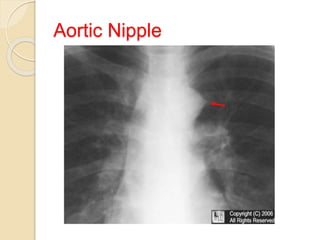

Aortic Nipple

 Seen as a small soft-tissue density adjacent

to the lateral border of the aortic knob on a

frontal radiograph.

 an aortic nipple is a radiological sign that

represents the left superior intercostal vein

as it runs around the aortic arch before

joining the left brachiocephalic vein.

 In certain conditions the aortic nipple can

become enlarged and mimic

lymphadenopathy or aortic aneurysm.

 No treatment is needed other than treatment

of the underlying condition.

Aortic Nipple…

Conditions that can cause an aortic nipple

are

a) Normal variant

is usually found in normal healthy patients in anywhere

from 1.4-9.5% of people.

b) Increase in venous flow such as

 Recumbant position, or during expiration

 Portal venous hypertension secondary to hepatofugal

shunting from the liver,

 congenital anomalies of the caval, azygos or

hemiazygos circulation results in enlargement of the left

superior intercostal vein.

 partial or total anomalous pulmonary venous drainage

c) Caused by increased venous resistance as in

 Congestive heart failure,

 Budd Chiari sydrome

 absence or obstruction of the inferior vena

cava

The left superior intercostal vein may act as

a collateral pathway, and therefore become

distended, in patients with impending or

actual superior vena caval obstruction

Impending Superior Vena Cava

Syndrome

 Detection of ‘aortic nipple’ on chest

roentgenogram predates the clinical

syndrome by 7 to10 weeks

 Development of SVCS requires severe

venous compromise, whereas the left SICV

(superior intercostal vein) may be more

sensitive indicator because of

Its small caliber,

Rapid distensibility,

Clearly defined and highly visible location

Capacity to greatly enlarge with increased

resistance